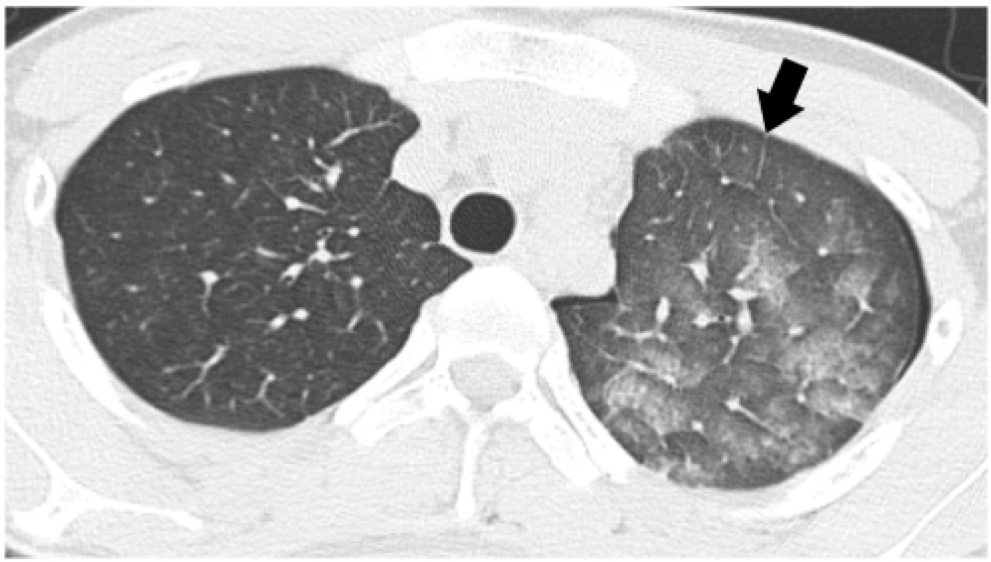

2,肺泡蛋白沉积症:1,复张性肺水肿:二,先介绍几种常见的良性ggo5,下表

1,复张性肺水肿:二,先介绍几种常见的良性ggo5,下表显示了所有可以